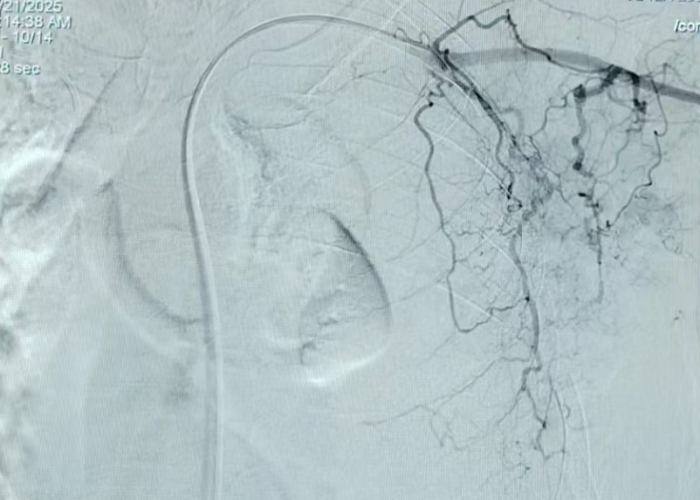

经过周密的术前准备,以肿瘤血液科行政副主任吴峰为主的介入团队,为患者施行了左锁骨下动脉栓塞术,该方案具有双重优势:其一,能高效杀伤肿瘤细胞,促使肿瘤迅速缩小;其二,通过栓塞血管极大减少肿瘤血供,从根源上显著降低坏死创面的出血风险,为后续清创创造了安全条件。

术中肿瘤造影

在精准的介入操作下,治疗成果立竿见影,肿瘤迅速缩小。由于肿瘤血供被有效阻断,后续处理坏死组织时,创面出血量极少,彻底改变了以往“一清创就大出血”的困境。随着介入治疗与后续创面管理的同步推进,张女士的病情迎来了根本性好转——困扰许久的恶臭消失了、痛苦的渗液停止了,久违的笑容重新回到了她的脸上。